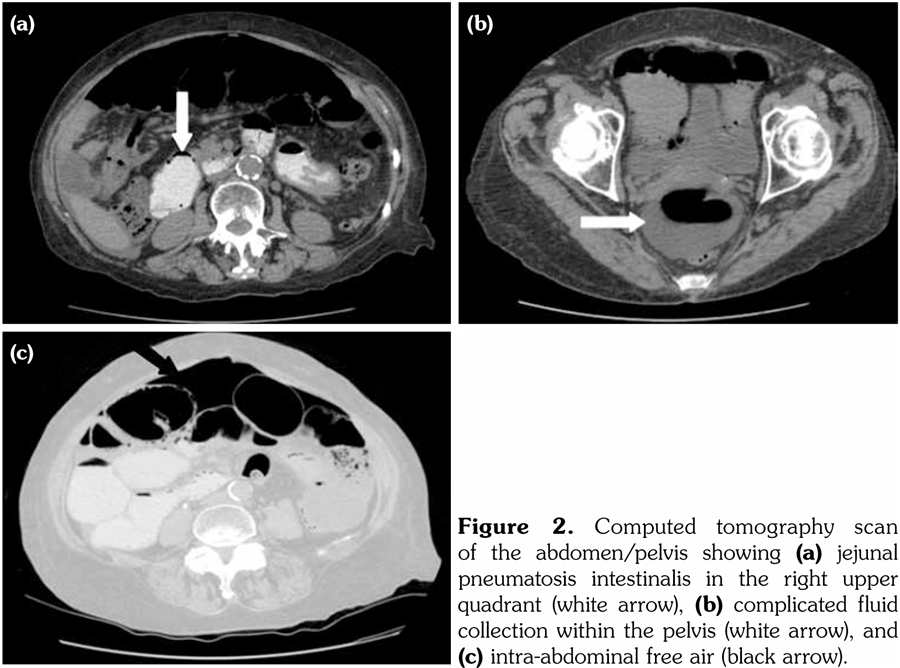

A 62-year-old female patient, diagnosed with mixed connective tissue disease (MCTD) five years priorly, presented with incidental findings of pneumoperitoneum on an outpatient chest X-ray (Figure 1). At initial diagnosis, she had inflammatory polyarthritis as evidenced by synovitis at the metacarpophalangeals and proximal interphalangeals bilaterally, Raynaud’s phenomenon, and swollen fingers (sausage appearance) with associated sclerodactyly. Serology showed positive anti-nuclear antibody (1:1200) and anti-ribonucleoprotein. All other autoantibodies were negative. She had initially been managed with oral steroids but was never on any immunosuppressant due to mild disease and patient preference. She had a history of vague abdominal discomfort, dysphagia and diarrhea since diagnosis, and did not report worsening of her baseline symptoms. On presentation to hospital, she was hemodynamically stable and her physical examination revealed a non-tender abdomen with no evidence of peritonitis. The patient had multiple comorbidities, which were severe chronic obstructive pulmonary disease, remote viral cardiomyopathy, small intestinal bacterial overgrowth (SIBO) and gastroesophageal reflux disease. She was not on corticosteroids, antibiotics or any immunosuppressant.